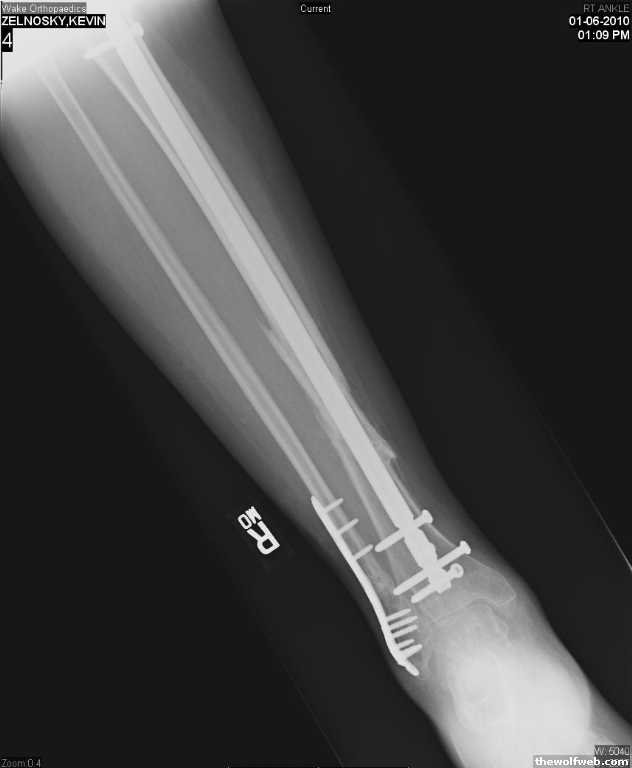

Photo Gallery » Zel » Ok, now fixed.....

Ok, now fixed... I think